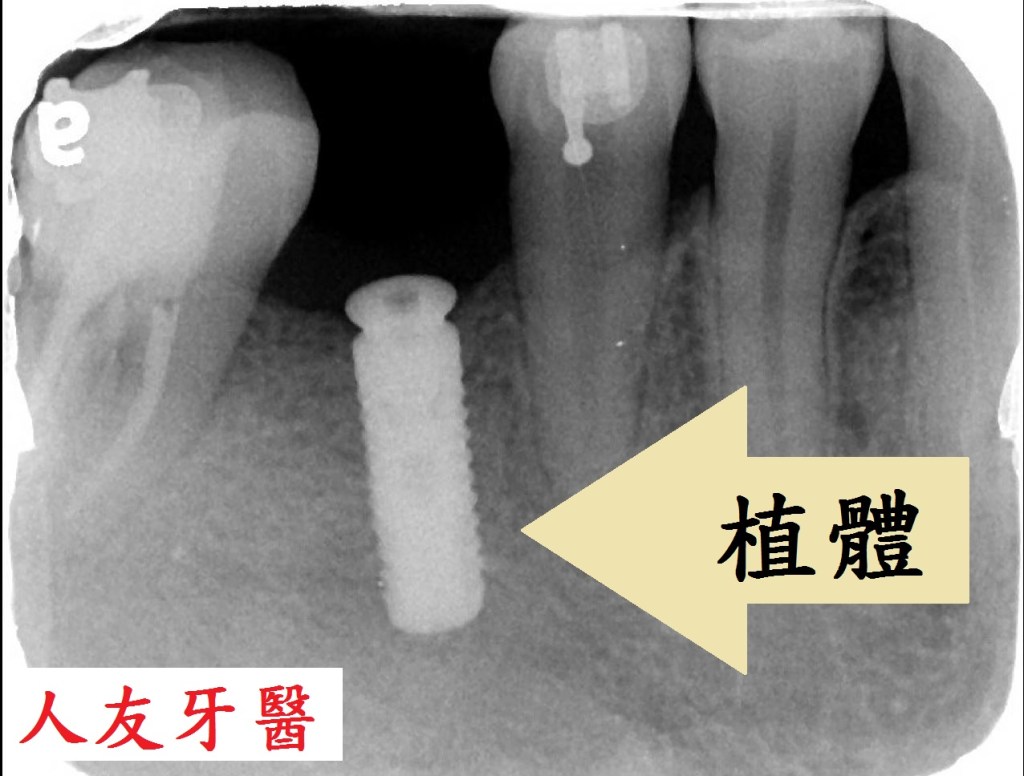

拔完牙後一個月,看傷口癒合情況,因兩顆門牙缺牙太久,齒槽骨流失比較多,醫師建議補骨跟植牙同時進行,植入三根牙根,位置分別在於右邊側門牙一顆,右邊正門牙和左邊側門牙。

再用左邊側門牙牙套搭橋到右邊正門牙牙套(三顆相連),右邊側門牙獨立做牙套。使門面變好看,說話也不會漏風。

植牙的人工牙根材質是衛署合格認證的醫療用鈦金屬,牙套是使用義大利原廠進口,也是衛署合格認證的全鋯牙冠,不含金屬,對牙肉有親和力。